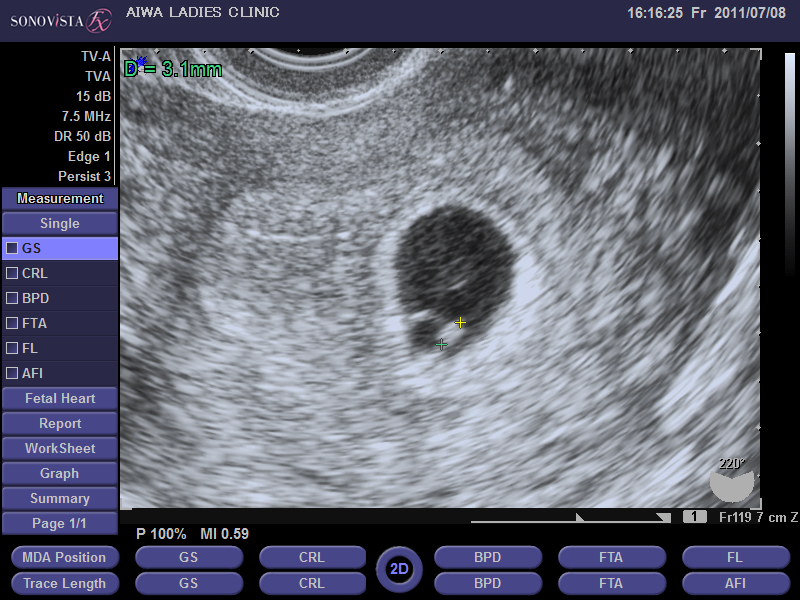

妊娠初期 胎嚢が小さいと言われてから心拍確認までの記録 よっちのパピルス帳

胎嚢が小さいと言われ不安だった話 妊娠判明 心拍確認 もものはなブログ

6w4d心拍確認できた エコーで確認した胎嚢のサイズや胎芽の大きさ つわりまとめ 晩婚だけど幸せ みゃーのアラフォー結婚生活ブログ